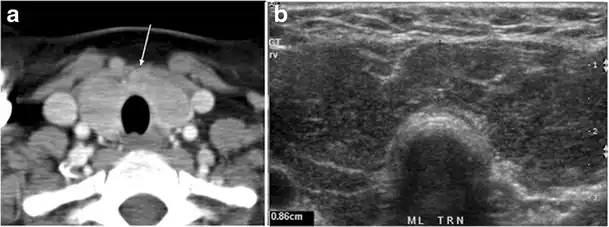

Fig. 15. A 33-year-old female patient who presented with neck swelling and pain and was later diagnosed with Hashimoto's thyroiditis. an Axial enhanced CT scan of the neck demonstrates minimal diffuse enlargement of the thyroid gland, especially the isthmus (white arrow). b Transverse greyscale ultrasound of the neck demonstrates heterogeneously enlarged thyroid and thickened isthmus, measuring 8.6 mm.[1]